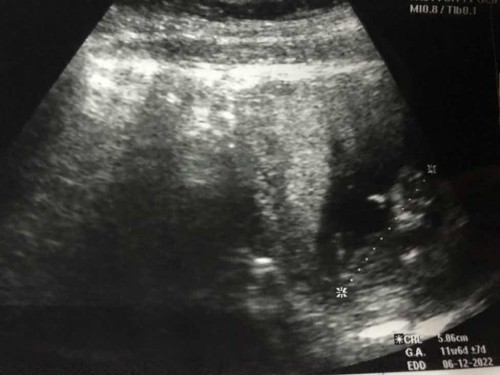

ท้องได้3เดือนนแล้วคะ

ทำไมน้องตัวยาวจัง แบบนี้ปกติไหมค่ะ หรือว่าน้องจะสูงได้พ่อเค้า🥰

ปกตินะคะ ในเกณฑ์ เด็กไม่ได้ยาวมาจากในครรภ์ขนาดนั้นค่ะ นี่สูง 173 สามีสูง 190 ลูกก็ไม่ได้ยาวพิเศษอะไร รอดูตอนโต ไม่ได้ยาวอะไรตอนนี้

ถ้าหมอไม่ได้แจ้งว่าผิดปกติไม่ต้องกังวลนะตัวเอง บ้านนี้ตอน 12w ก็ 6 เซนกว่าเหมือนกัน❣️

อยู่ในเกณฑ์ปกติค่ะคุณแม่ บ้านนี้3เดือนกว่าๆๆ ประมาณนี้เลยค่ะ🥰

11วีค 6 วัน 5ซม. อยู่ในเกณฑ์ปกติค่ะแม่